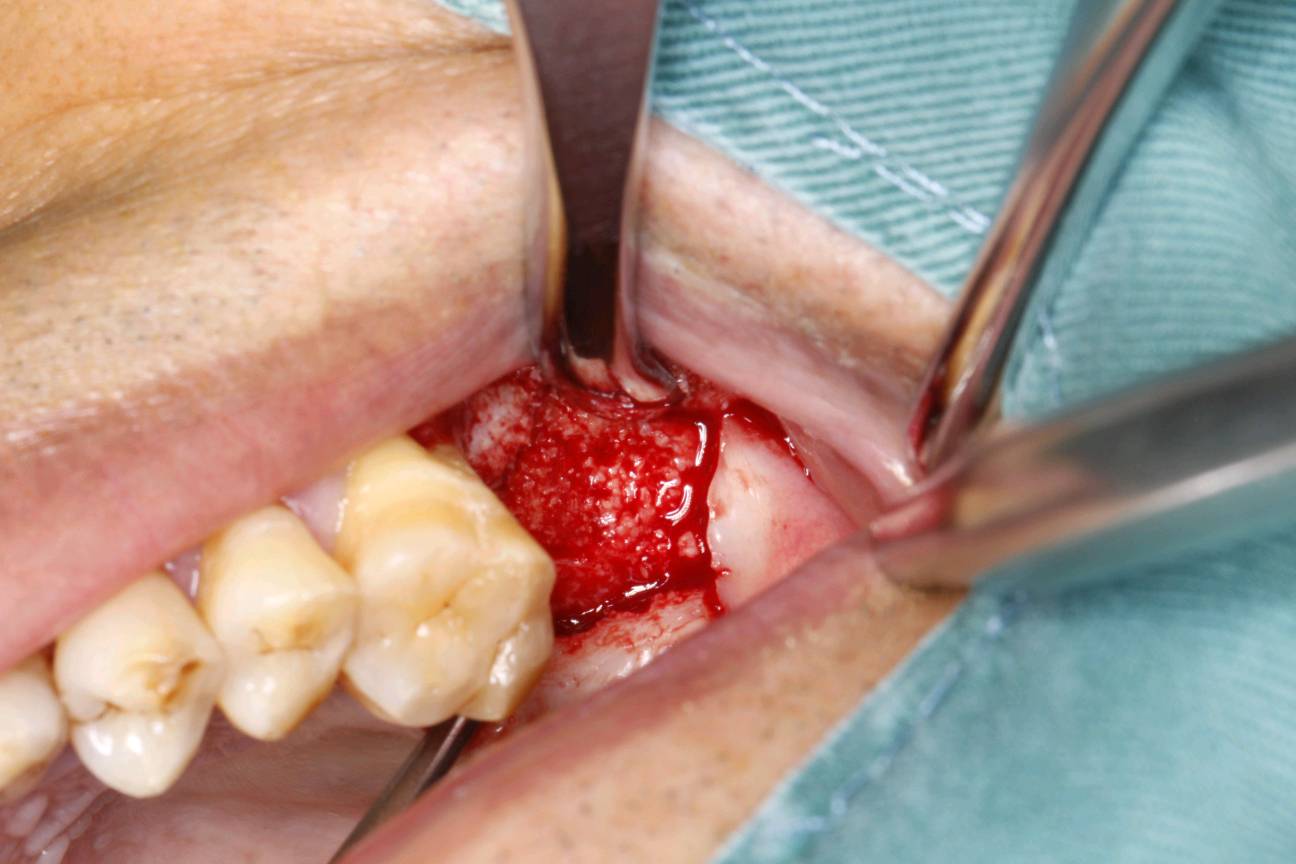

患者知情同意下,抽静脉血30ml,制作 CGF ,0.1%聚维酮碘溶液口内粘膜消毒,0.5%聚维酮碘溶液口外皮肤消毒,4%盐酸阿替卡因肾上腺素注射液2.0ml浸润麻醉,牙槽嵴顶切开粘骨膜,翻瓣。见腭侧大面积骨缺损,球钻定位,先锋钻导向,骨质钻扩大种植窝,行上颌窦内提,特殊冲顶器械敲击,抬高上颌窦底部骨质和黏膜。并攻丝植入 ITI 种植系种植体4.8*8mm,上封闭螺丝,腭侧骨缺损区植 bio - oss 骨粉0.25g及 CGF ,并盖 bio - Gide 膜及 CGF 膜,严密缝合,常规医嘱,15天拆线,抗生素自备。